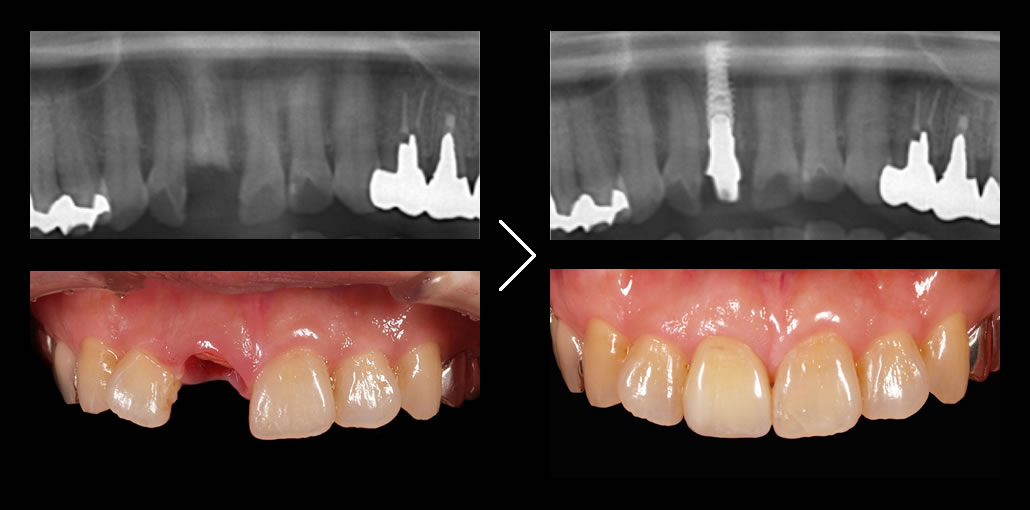

当院が最も得意とするのが前歯のインプラントです。

奥歯(臼歯部)で、十分な骨がある場合のインプラントは極めて簡単です。一方、インプラントを固定する骨が十分にない前歯のインプラントが最も難易度が高くなります。前歯は目立つため、見た目の美しさを気にして患者様の要求水準が高まるのも前歯のインプラントの特徴です。 こういった症例では、技術的に難しいため、インプラント治療ではなくブリッジでの治療を勧める歯科医院が多いのが現実です。

しかし、ブリッジの場合、歯のない部分の歯ぐきが時間の経過とともにどんどん痩せていくため美しい見た目を維持することは困難です。又、健康な歯を削ってしまうことは最大のデメリットです。

私たちが最も得意とするのがこの前歯のインプラント治療(審美インプラント)です。誰が見てもインプラントと分からない水準で仕上げることが可能です。